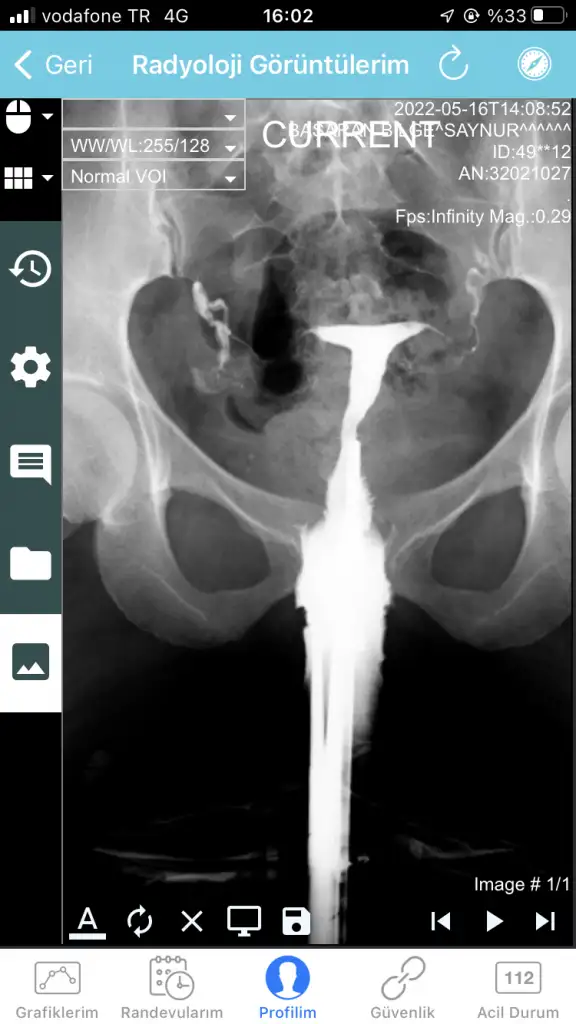

Kızlar merhaba, bugün Hsg çektirdim. Görüntülerine bakabilir misiniz tecrübeli arkadaşlar

İlk yorumu yapan olmadı mı çekimden sonra🙃 T görünümü var ama raporda şekil bozukluğu ile ilgili bir ibare yok. Ancak sol tüpün tıkalı olabilir 🤔 genel bi başlık aç istersen daha çok yazan olur inşallah ben yanlış algılamışımdır

Merhaba , tıkanıklık bu filmde açılabiliyor mu hiç bilmiyorum . Doktor yorum olarak kapalı görünüyor sanki ama ben sıvı geçişini gördüm aslında kapalı değil dedi . Anlamadım . Yani filme baktığımızda ince bir çizgi gibi geçiş var . Doktora göre de var , raporda kapalı olduğu yazıyor .